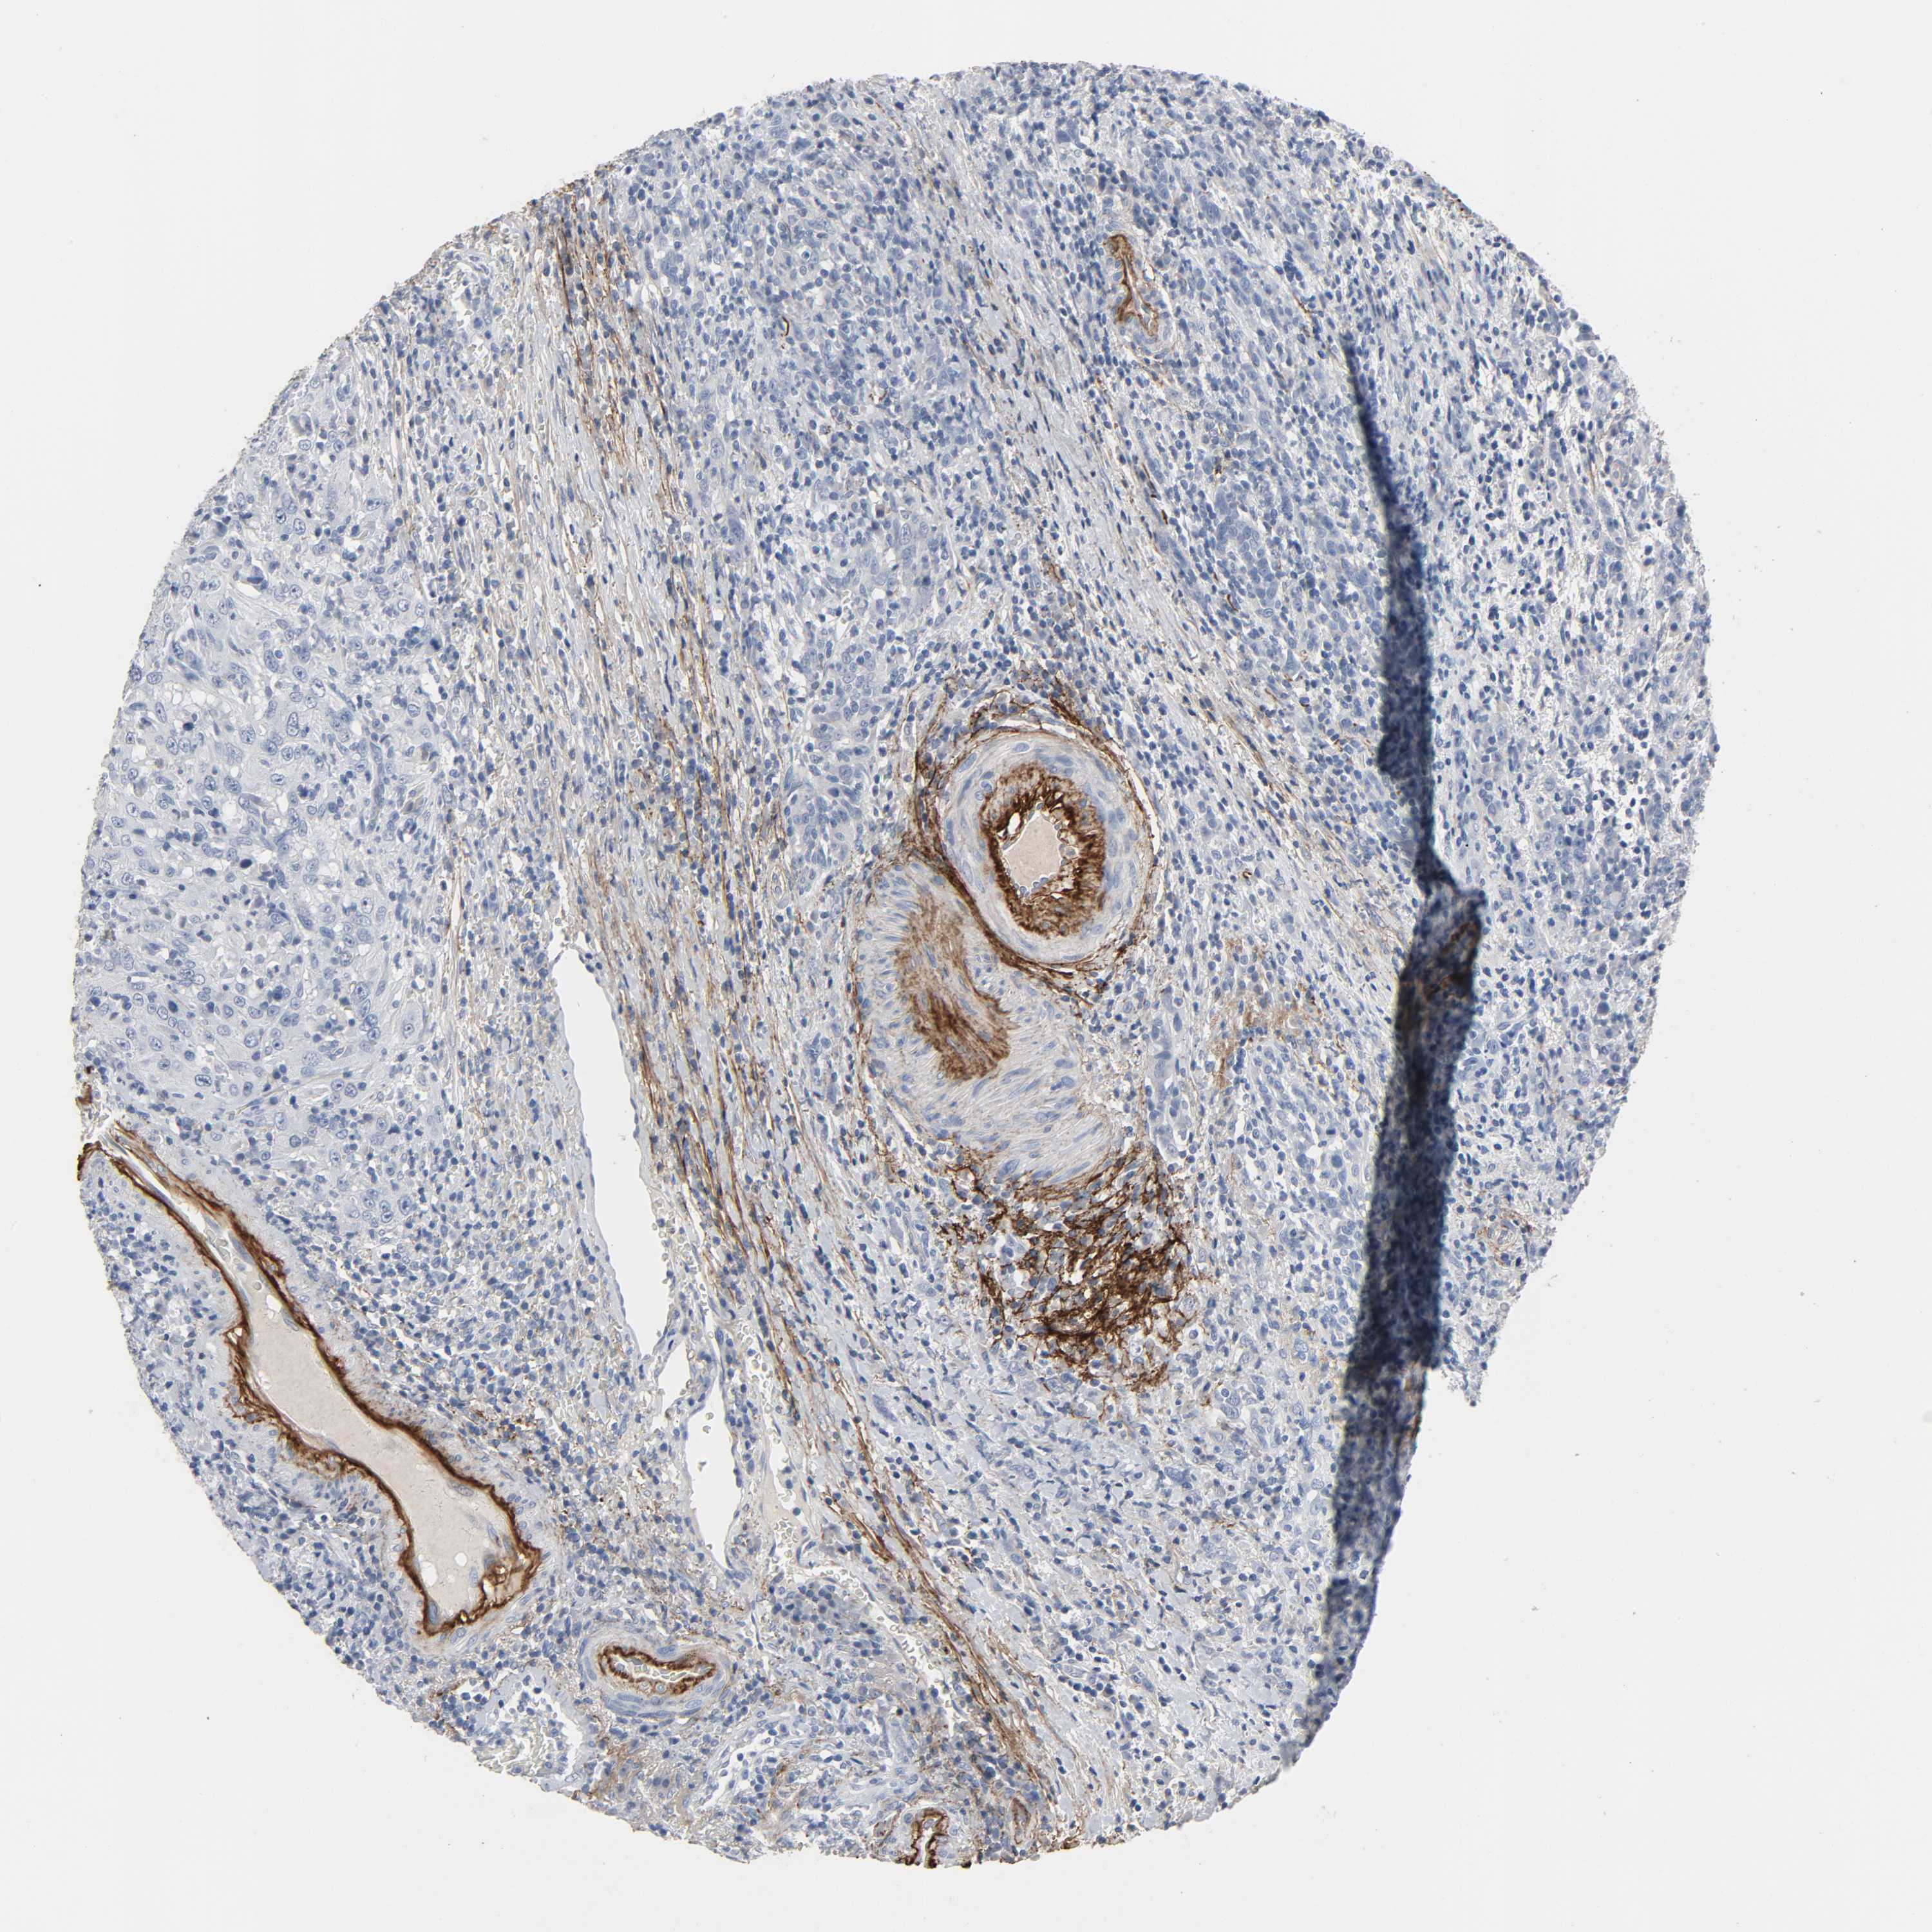

UROTHELIAL CANCER - Protein expressioni

A mouse-over function shows sample information and annotation data. Click on an image to view it in a full screen mode. Samples can be filtered based on level of antibody staining by selecting one or several of the following categories: high, medium, low and not detected. The assay and annotation is described here.

Note that samples used for immunohistochemistry by the Human Protein Atlas do not correspond to samples in the TCGA dataset.

Antibody stainingi

Antibody staining in the annotated cell types in the current human tissue is reported as not detected, low, medium, or high, based on conventional immunohistochemistry profiling in selected tissues. This score is based on the combination of the staining intensity and fraction of stained cells.

Each image is clickable and will lead to virtual microscopy that enables deeper exploration of all samples and also displays staining intensity scores, fraction scores and subcellular localization as well as patient and tissue information for each sample.

Antibody HPA000848

Antibody HPA000868

Antibody CAB025843

Staining

High

Medium

Low

Not detected

Intensity

Strong

Moderate

Weak

Negative

Quantity

>75%

75%-25%

<25%

None

Location

Nuclear

Cytoplasmic/membranous

Cytoplasmic/membranous,nuclear

Urothelial carcinoma, High grade

Urothelial carcinoma, Low grade